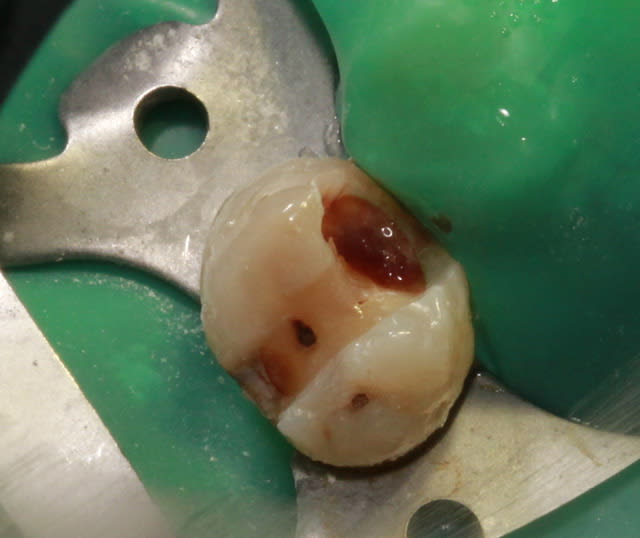

Question "shopping": Quel est le matériau d'étanchéification (bleu) que tu as utilisé, et se substitut-il à un clamp?

Merci.

1 hkievk - Eugenol

lupusebastian

11/12/2012 à 08h38

bonjour!

le materiel e LC BlockOut Ultradent (une resine per lab)